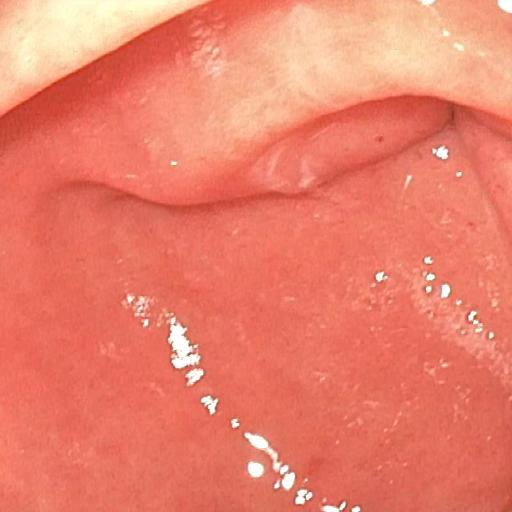

| (a) Input | (b) LIME | (c) HDRNet | (d) LECCM | (e) SwinIR | (f) NAFNet | (g) EndolMLE | (h) Ours | (i) GT |

The proposed method was evaluated on a synthetic dataset. All deep learning-based methods were fine-tuned based on E-kvasri. Figure 2 presents sample results of the proposed method and comparative methods on four endoscopic images from the E-kvasri.